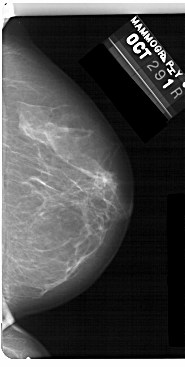

A_1477_1.LEFT_CC

LEFT_CC LINES 5491 PIXELS_PER_LINE 2746 BITS_PER_PIXEL 12 RESOLUTION 43.5 OVERLAY